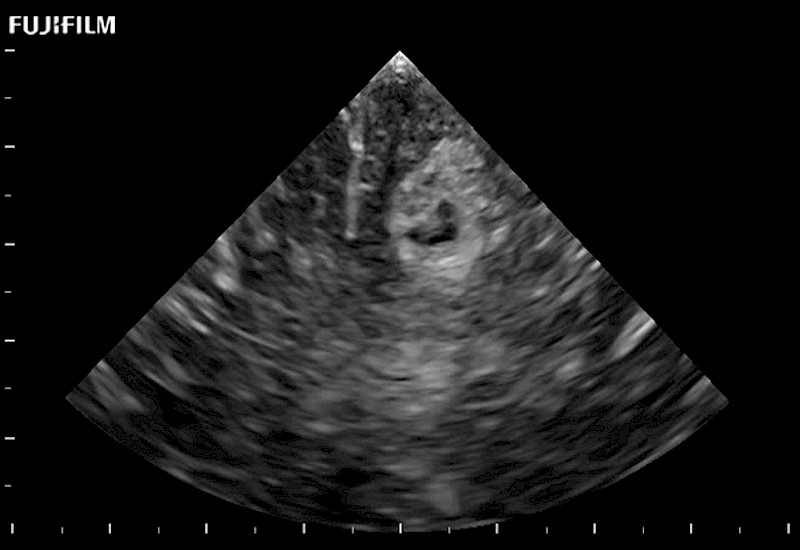

Extraordinary high-resolution digital imaging

Exceptional transducers

for use during: Cranial guidance, Burr-Hole guidance, Spinal Cord guidance, Pituitary guidance, Micro-Surgery guidance

Our dedication to neurosurgery allows us to offer superior image quality, outstanding system reliability and intuitive use of cutting edge technology.